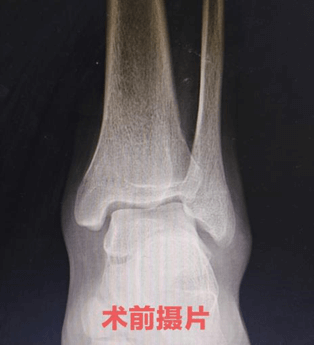

患者张某某,男,15岁,学生。6年前曾有左踝扭伤史,接受过石膏固定。近日运动时再次扭伤左踝,出现明显肿胀、疼痛,活动受限。我院MRI检查提示:距腓前韧带撕裂,伴关节周围软组织水肿。

骨伤一科王东主任指出:结合患者病史、体征及影像学结果,明确诊断为左踝距腓前韧带撕裂。该患者既往有踝关节扭伤,此次再次受伤,查体显示左踝前抽屉试验和内翻应力试验均为阳性,存在明显韧带松弛,影像学也确认韧带撕裂。经与患者及家属充分沟通,建议行手术治疗(距腓前韧带修补术——踝关节稳定术),家属同意并积极配合。排除手术禁忌后,王东主任为患者实施手术,过程顺利,术后予石膏外固定制动。